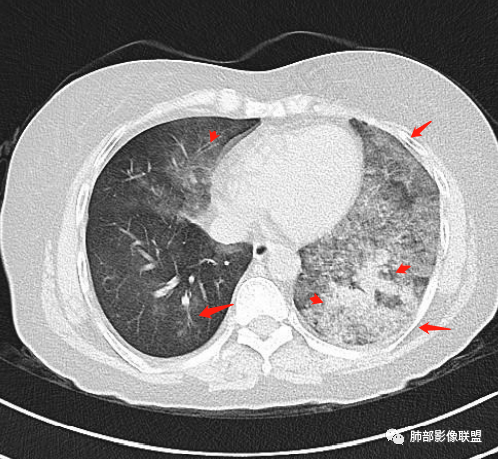

小兜:女,57岁,间断咳嗽1月,咳白色粘痰。CT示左肺下叶实变影,周围可见大片磨玻璃密度影,右肺亦见少量斑片状磨玻璃密度影。考虑恶性可能,左肺下叶粘液腺癌伴播散。

宇宙:两肺多发磨玻璃影,边缘模糊,左肺为著,左肺下叶伴实变,增强实变不均匀强化,其内支气管有阻塞、扩张,考虑粘液腺癌。

飞鹰行动:病史较长,左肺下叶实变及周围磨玻璃影,增强可见血管造影征,考虑左肺下叶粘液腺癌。

放射线:左肺下叶实变及双肺磨玻璃影,左下肺病灶周围磨玻璃影,有重力作用,呈叠瓦片状,增强可见血管造影征,考虑左肺下叶粘液腺癌伴双肺播散。

放射小白:中年女性,间断咳嗽一月余,咳痰4天;影像表现:右肺中下叶、左肺下叶见磨玻璃密度影,左肺下叶局部可见实性密度影,实性成分内部可见变窄、截断支气管通气征,增强实性成分内部可见血管造影征,但是血管扭曲,结合以上分析两肺符合肺黏液腺癌,不排除肺腺癌。

患者,女性,57岁。咳嗽1月、咳痰4天,亚急性病史,抗炎效果不佳,体温不高,痰为白色黏痰,白细胞稍高,主病灶在左下叶,实变+GGO,其余肺也有GGO,伴随有结节。

本例病例老年女性,慢性病程,抗炎效果不佳。CT示左肺下叶实变影,周围可见大片磨玻璃密度影,密度不均。右肺亦见少量斑片状磨玻璃密度影。增强可见血管造影征,结合南大分析,排除真菌,结核等,答案就呼之欲出了。